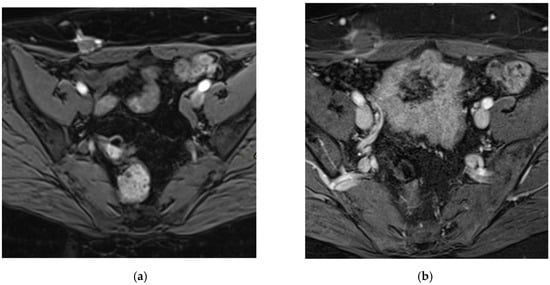

- Radzynski, L.; Boyer, L.; Kossai, M.; Mouraire, A.; Montoriol, P.-F. Pictorial essay: MRI evaluation of endometriosis-associated neoplasms. Insights Imaging 2023, 14, 144. [Google Scholar] [CrossRef] [PubMed]

- Hu, S.; Liu, Y.; Chen, R.; Xiao, Z. Exploring the Diagnostic Performance of Magnetic Resonance Imaging in Ultrasound-Guided High-Intensity Focused Ultrasound Ablation for Abdominal Wall Endometriosis. Front. Physiol. 2022, 13, 819259. Available online: https://www.frontiersin.org/journals/physiology/articles/10.3389/fphys.2022.819259/full (accessed on 17 March 2025). [CrossRef] [PubMed]

- Busard, M.P.H.; Mijatovic, V.; van Kuijk, C.; Hompes, P.G.A.; van Waesberghe, J.H.T.M. Appearance of abdominal wall endometriosis on MR imaging. Eur. Radiol. 2010, 20, 1267–1276. [Google Scholar] [CrossRef] [PubMed]